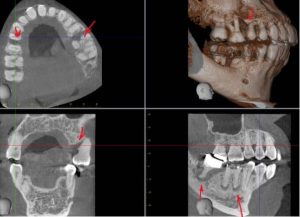

This Africo-Carabian lady presented with the following Clinical & Radiographic FindingsLower Left Quadrant (LLQ) – [...]